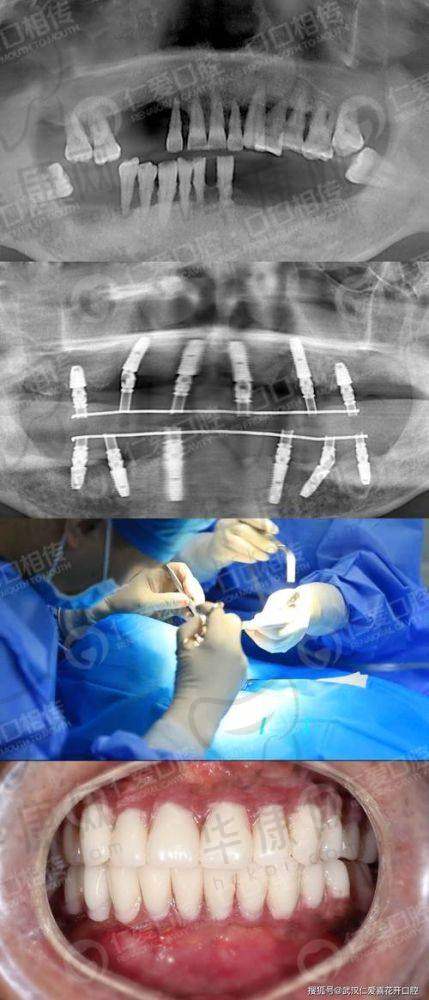

为了制定更精细的种植方案,何春秀医生安排我做了一系列详细的检查,包括口腔CT、X光片等。检查过程中,医护人员都特别细心,操作也特别熟练,尽量减少我的不适感。检查结果出来后,何医生拿着片子,一点一点地给我讲解我的口腔状况,指出了存在的问题以及适合我的种植方案。她告诉我,我的牙槽骨条件还不错,可以进行全口即刻种植牙手术,这让我看到了希望。

湖南湘西口腔医院何春秀全口即刻种植牙之手术过程

湖南湘西口腔医院何春秀全口即刻种植牙之术后修复

术后的修复阶段,我严格按照何春秀医生的嘱咐进行护理。刚开始的时候,口腔会有一些轻微的肿胀和疼痛,但这都是正常现象。何医生会定期打电话回访我的修复情况,还提醒我按时来医院复查。每次复查,她都会仔细检查我的种植体愈合情况,根据修复情况调整护理方案。在她的精心指导下,我的修复情况非常好,种植体和牙槽骨结合得特别紧密。